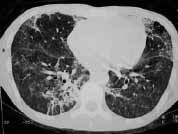

En la radiografía de tórax se evidenciaron infiltrados de ocupación alveolar en parche de distribución periférica. El ecocardiograma mostró miocardiopatía dilatada en fase leve y signos indirectos de hipertensión pulmonar.

Además del antecedente de inyección subcutánea de silicona, y teniendo en cuenta su mayor relación con múltiples inyecciones y mayor cantidad de sustancia, el hallazgo radiológico de infiltrados alveolares periféricos que afectan principalmente la corteza pulmonar es muy sugestivo de embolismo de esta sustancia.

Ante la presencia de edema pulmonar de permeabilidad o hemorragia alveolar estos infiltrados pueden hacerse difusos. La TACAR resalta este hallazgo, y se suma la presencia de engrosamiento de líneas septales probablemente relacionadas con diseminación linfática de silicona.

Figura 5. TACAR: Demuestra la presencia de áreas de vidrio esmerilado difuso e infiltrados alveolares en parches, secundarios a hemorragia alveolar y embolismo por silicona.